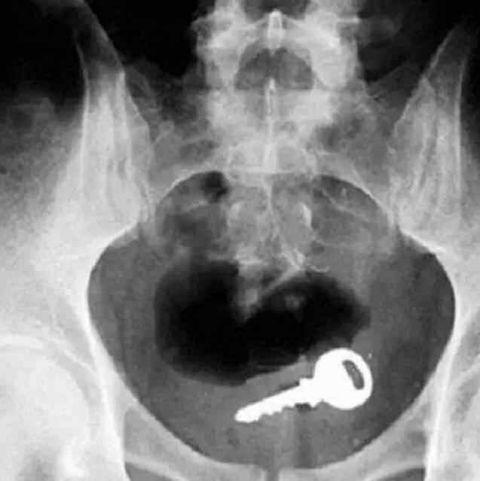

一把钥匙